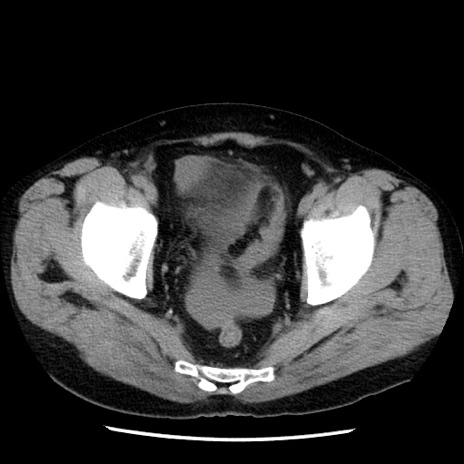

症例29(横断像)

【症例】40歳代男性

【現病歴】2日前から胃痛あり。徐々に周期的な激痛に変化した。本日になっても激痛があるため受診。

【身体所見】意識清明、BT 38-39℃台あり、腹部:膨満、やや硬、右下腹部に圧痛あり。

【データ】WBC 8500、CRP 23.26